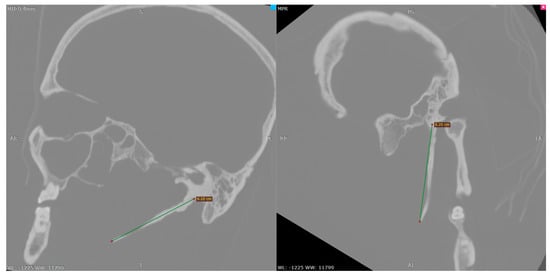

| Anatomical landmarks | Multiplanar reconstruction using the orbito-meatal sagittal plane, with oblique adjustment of the axial plane. Length: 62 mm measured in the sagittal plane; the distal portion shows a slight curvature. |

| Reference planes | Dimensional assessment from the inferior surface of the petrous part of the temporal bone |

| 3D Model | 3D reconstruction—length: 61 mm |